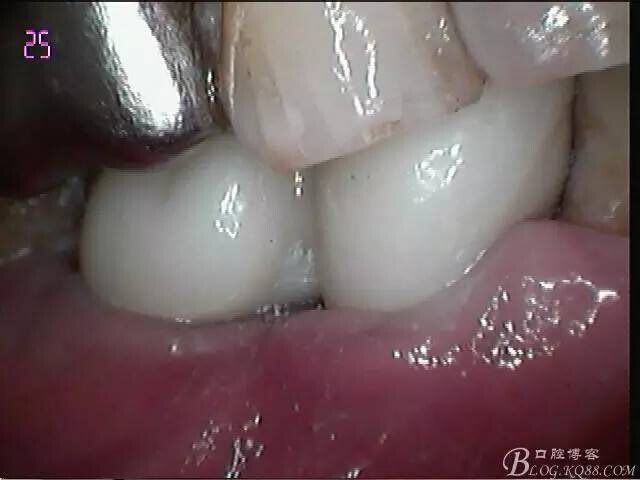

口外粘接后,口內螺絲固位

檢查邊緣封閉及靜態(tài)密合

牙齦封閉良好,咬合,近中觸點穩(wěn)定

樹脂封閉螺絲孔